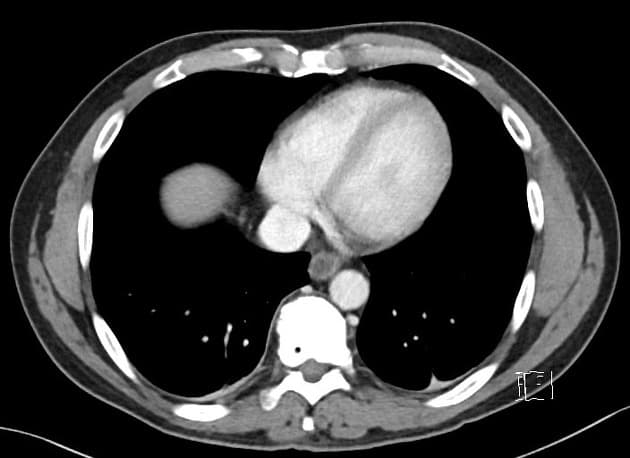

Ileocecal tuberculosis with intestinal obstruction

Air Bronchogram in Pneumonia (Hiện tượng phế quản khí trong viêm phổi)